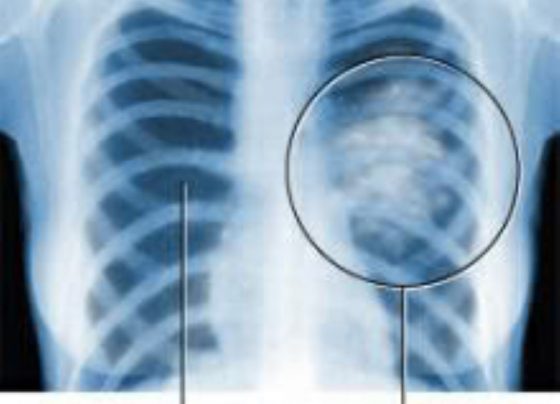

Improved Detection, Awareness Needed To Counter TB: Malaysian Official

KUALA LUMPUR, Mac 25 (NNN-BERNAMA) – Improving detection and raising awareness are needed, to eradicate tuberculosis (TB), a Malaysian official…